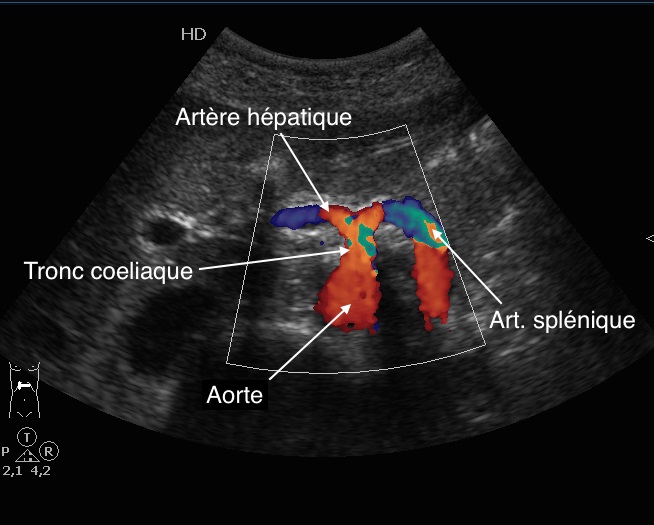

Avec coupe transverse a travers le

tronc coeliaque , arterte hepatique peut en

s'observe a droit du tronc coeliaque " signe de

mouette " |